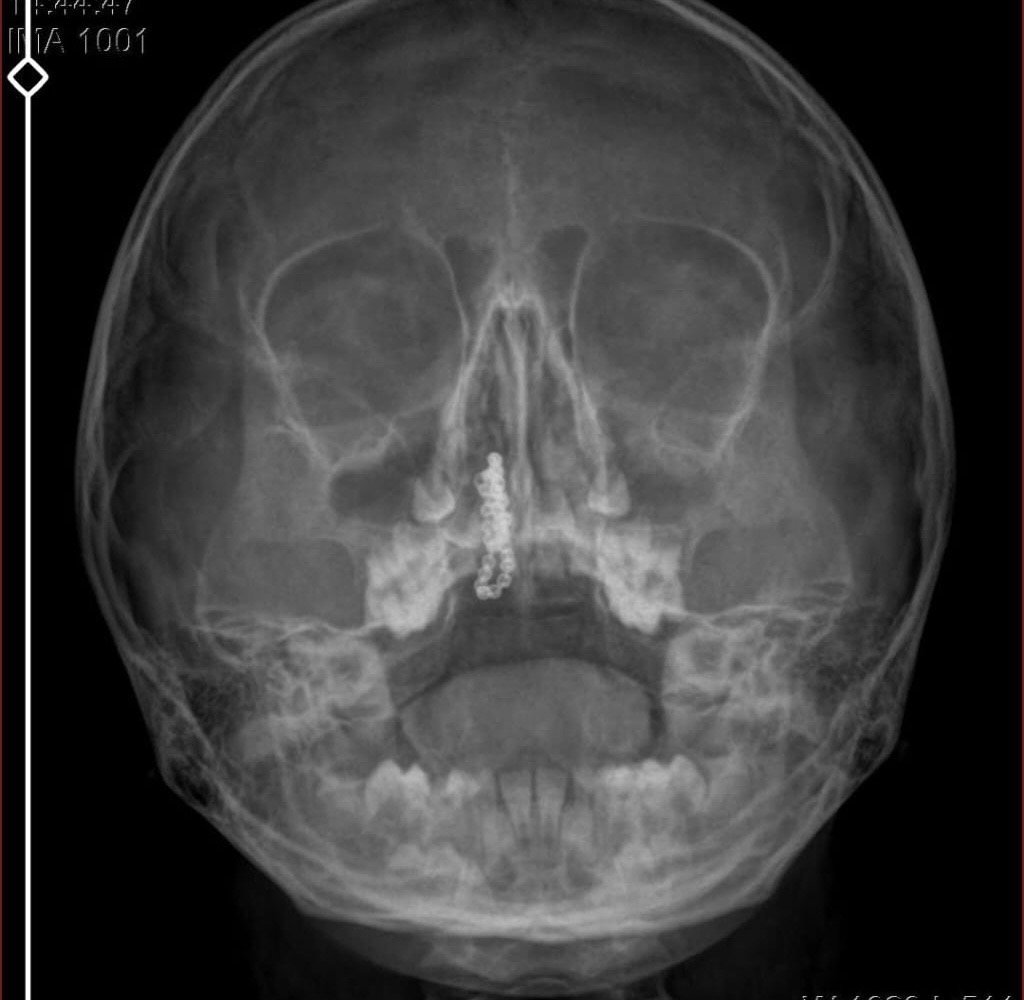

Kentte yaşayan Gökhan-Nalan Tekin çifti, yaklaşık 4 ay önce şiddetli burun kanamasının yanı sıra akıntı şikayetleriyle kızları Polen’i, bir özel hastaneye götürdü. Burada röntgeni çekilip, tetkikleri tamamlanan küçük kıza, iddiaya göre enfeksiyon teşhisi konulup, ilaç verildi. Eve dönen aile, kanama ve akıntının geçmemesi üzerine bu kez Rize Devlet Hastanesi’ne giderek Kulak Burun Boğaz Polikliniği’ne başvurdu. Devlet hastanesindeki doktorun incelemesi ve kapsamlı röntgen çekilmesi sonrası Polen’in burnunda metal cisim olduğu fark edildi. 2 yıldır burunda kaldığı değerlendirilip, küçük top şeklinde tırnak makası zinciri olduğu belirlenen cisim, başarılı ameliyatla çıkarıldı. Bir süre tedavisi sürdürülen Polen, sağlığına kavuşunca taburcu edildi. Özel hastane yetkilileri, konuyla ilgili açıklama yapmazken; aile suç duyurusunda bulunacaklarını söyledi.

Kızının burnundan sürekli siyah renkte akıntı olduğunu anlatan Gökhan Tekin, “Çocuğumun burnundan kanama ile sürekli siyah akıntı geliyordu. Özel hastaneye götürdüm. Özel hastanede film çekildi, hiçbir bulguya rastlanılmadığı söylendi. O siyah leke de enfeksiyona dayalı olan bir şey olduğu bize söylendi. Eve geldik, akıntı sürmesi üzerine bu kez devlet hastanesine başvurduk. Burunda metal zinciri fark ettiler. Böyle bir ihmalkarlık olabilir mi? Özel hastaneye gidiyoruz, paramızla rezil oluyoruz. Zincir, 2 yıldır burnunda ve devletimizin hastanesinde iyi bir doktorumuz zinciri ortaya çıkarıyor, kızım ölümden dönüyor. Ben sonuna kadar bu işin peşini bırakmayacağım. Sonuna kadar hukuk mücadelesi vereceğim. Bu da diğer hastalarımıza ibret olsun. İşte, bakın koca bir zincir. ‘Bulguya rastlanılmadı’ deniliyor” dedi.

Kızının ameliyat sonrası durumunun iyi olduğunu söyleyen Tekin, “İnanır mısınız bize ‘Evde soba mı yanıyor? Acaba kömür isten dolayı mıdır bu?’ dendi. Böyle bir şey olabilir mi? Ameliyattan çıkan parmağım kadar zincir. Devlet hastanesindeki doktor da ‘Bu nasıl gözden kaçılabilir? Böyle bir pozisyon nasıl görülmeyebilir?’ yorumunda bulundu. Allah’a şükür olsun atlattık. Şu anda durumu, vaziyeti iyidir. Ben şuna inanıyorum doktor da bir şans işidir. Bakın paramızla özele gideriz ya hani bizde, daha iyi ilgilenirler. Oysa devlet hastanesindeki doktorumuz olayı meydana çıkardı” diye konuştu. (DHA)